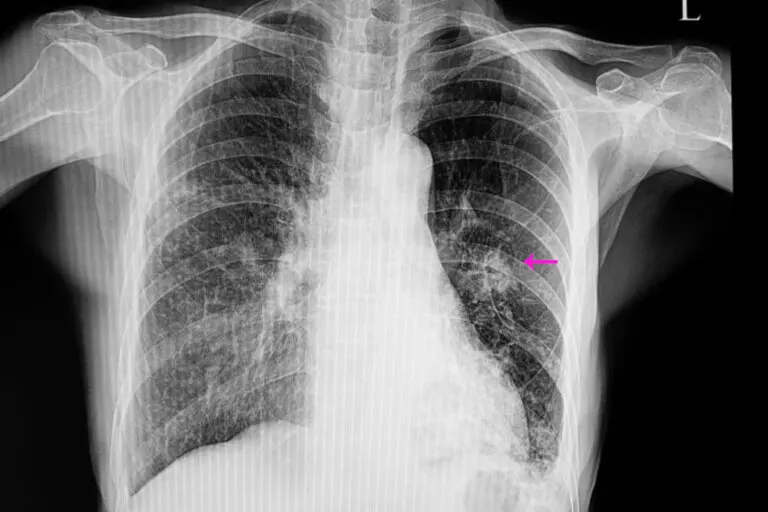

El examen médico se complementa con pruebas de imágenes y, de ser necesario, una biopsia

Una vez hecho esto, es necesario realizar ciertas pruebas de imagen para localizar el nódulo. Además, las imágenes permiten observar ciertas características como la forma y el tamaño, que son importantes para diferenciar uno benigno de uno posiblemente maligno.

Las más utilizadas son la radiografía de tórax y la tomografía computarizada. Para conocer exactamente la causa del nódulo pulmonar, en ocasiones se realizan biopsias que permiten analizar el tejido que lo forma.